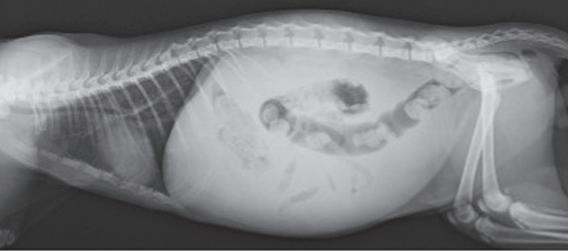

Figure 1. A British short haired cat from Hong Kong with wet (effusive) FIP. Picture Dr Chris Simpson Figure 3. Whole cat radiograph of the patient in Figure 1 with wet FIP Figure 2. High protein, strawcoloured fluid from the abdomen of the cat in Figure 1